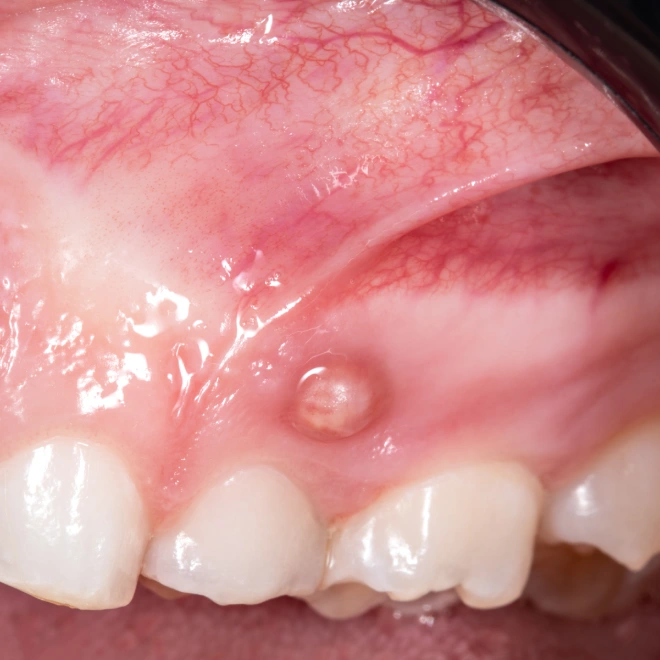

Свищ (синус-тракт) – это дренирующий канал, через который организм выводит гной из глубины тканей на поверхность слизистой (иногда даже на кожу лица). По сути, это «аварийный выход»: давление в очаге воспаления снижается, поэтому боль может уменьшиться или исчезнуть.

Свищ действительно может выглядеть как маленькая белая или желтоватая точка, иногда с выделениями. Но по природе это другое.

Как выглядит свищ на десне?Ответ на вопрос